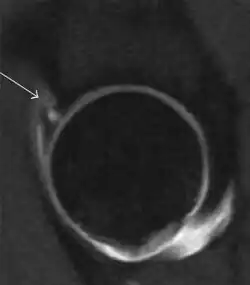

During childhood, ultrasound is a quick method to assess hip pain and quite often may be used to avoid use of irradiating techniques, such as radiography or CT. Ultrasound allows evaluation of joint effusion, synovial thickening and neovascularity, the bone/cartilage contour, and the femoral head-neck alignment. Although sonography is extremely sensitive in detecting increased synovial fluid, it is nonspecific and cannot be used with accuracy to determine the type of fluid. Transient synovitis of the hip, despite being the most frequent cause of pain in children between 3 and 10 years, remains a diagnosis of exclusion. It usually shows anechoic fluid, but echogenic fluid can also be found. The effusion is considered pathologic when it is measured at >2 mm in thickness. The differential diagnosis is wide, including osteomyelitis, septic arthritis, primary or metastatic lesions, LCPD, and SCFE. Discrimination from septic arthritis is challenging, often requiring joint aspiration. In septic arthritis, US is able to demonstrate a hip joint effusion, synovial thickening, and cartilage damage, although the appearances are nonspecific.[1]

Joint effusion in transient synovitis of the hip. -